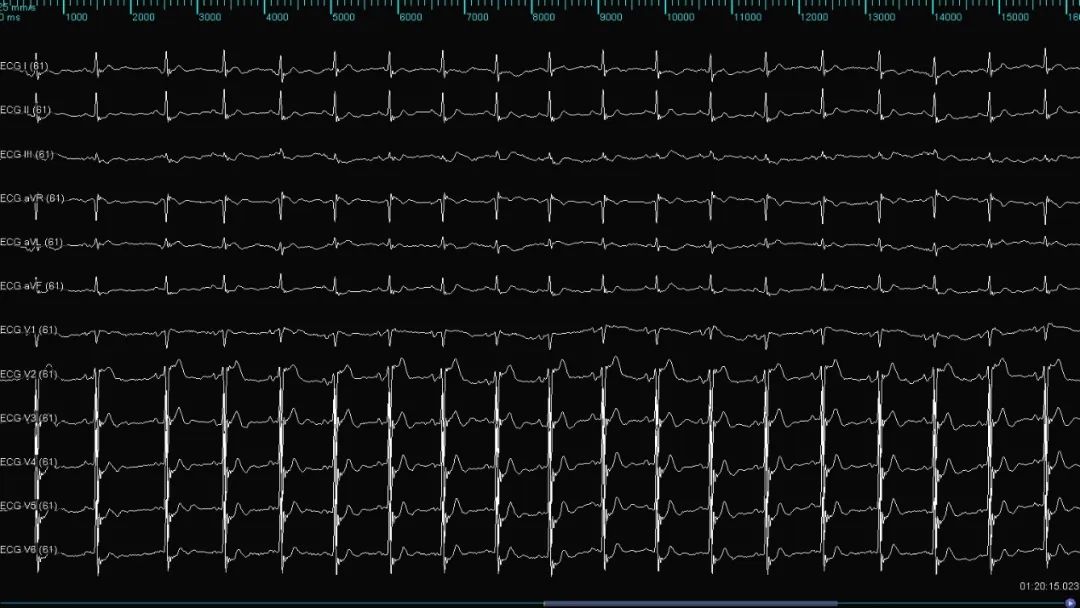

使用HD Gird重建左房三维模型,左房基质良好,首先完成肺静脉电隔离术(图1)。双侧肺静脉电隔离后,房颤转为房扑,经拖带标测提示为右房峡部依赖性房扑(图2),行三尖瓣峡部线性消融,消融过程中房扑终止转为窦性心律(图3),术后患者稳定窦性心律(图4)。

图1:双侧环肺静脉电隔离后转为房扑(房扑周长220ms)

图3:房扑终止,转为窦性心律

图4:术后患者稳定窦性心律